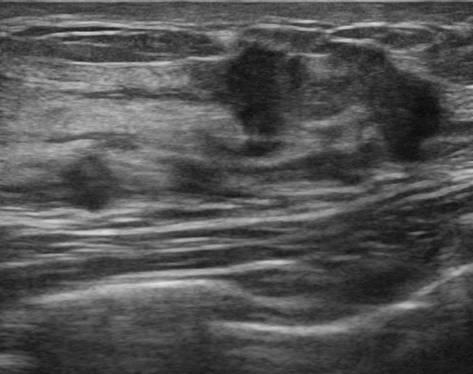

Ung thư vú

» Thông tin: Nữ giới – 25 tuổi.

» Lâm sàng: Khối tuyến vú.